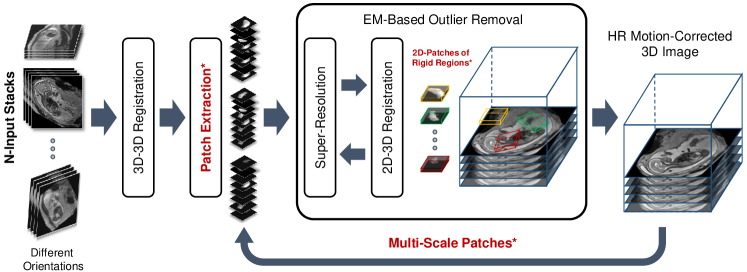

PVR relies on the fact that certain regions of the scanned anatomy are rigid and can be reconstructed with SVR super-resolution algorithms. However, unlike SVR, it is fully automatic and provides a full field of view reconstruction. Data consistency is obtained by oversampling a region of interest at different scan orientations. Robust statistics can be used to identify mis-registered or heavily corrupted data [24, 25]. Fig. 4 depicts a schematic overview of the proposed PVR framework.

Input Data & Initialization: A template stack is either randomly or automatically chosen from available input stacks by detecting the stack with the least motion artifacts [17]. Global intensity matching is applied to normalize intensity values of all input images followed by global 3D-3D alignments to spatially initialize the reconstruction target. Input data can be represented as stacks of 2D images (patches) consisting of

Patch to Volume Registration: An HR-image is reconstructed from a number of motion corrupted patches using 2D-3D registration-based super-resolution similar to [25, 17], where an accurate PSF calculation is used to generate a gradually improving approximation of and further employed to initialize the 2D-3D registration and computation of robust statistics. In [25, 17], the PSF equals to a sinc function for the in-plane and the slice profile for the through-plane, measured for the employed MRI sequence (ssFSE), according to [23].

During the optimization process, individual 2D patches are continuously rigidly registered to the current 3D reconstruction of and reintegrated into using iterative super-resolution with gradient descent optimization. Any similarity metric can be used as a cost function for the registration step such as mutual information [12, 25], cross correlation (CC) [23, 17], or mean square intensity differences [13, 24]. Choosing the best similarity metric for reconstruction depends on the input data. CC has been found to be effective for input data with similar intensity distribution [30]. In our experiments, we employ CC as the similarity metric for 2D-3D registration, after rescaling the intensities between the input stacks.

EM-Based Outlier Removal: Correctly registered patches should provide a higher contribution to the final reconstruction, presenting with a low error when compared to the original image data. [24] initially introduced an approach to account for outliers during super-resolution based on Huber function statistics. Similar to [25], we employ the expectation maximization algorithm for outlier removal by classifying and the included pixels into an inlier and outlier class. A zero-mean Gaussian distribution with variance is used for the inliers and a uniform distribution with constant density